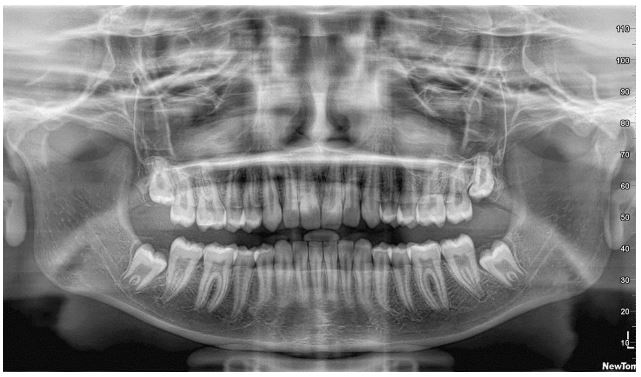

On presentation, the patient had a panoramic radiograph, where the TMJ depicted rather atypical (Figure 4). The diagnostic process could not rely on this x-ray, due to the overlaps with other anatomical elements in the region; this additional imaging techniques deemed necessary [14]. The Cone beam computed tomography (CBCT) which was selected in this instance, revealed on the right side that the condyle was centrally positioned, while erosive lesions were seen in the upper anterior region of the condyle at the medial pole. Microerosions at the outer pole could not be ruled out. Early to moderate degenerative alterations were consistent with this image (Figure 5).

On the left side, the condyle was posteriorly displaced, although the joint space remained within the expected range. An extensive erosive lesion, approximately about 5 mm in diameter was evident in the posterior- superior portion of the condyle. This lesion occupied the whole middle third of the condyle head and was surrounded by a sclerotic margin. This image was indicative of a higher degree of degenerative alterations (Figure 6).

Figure 5: The cone beam computed tomography (CBCT) image of the right TMJ in close mouth position. The condyle was centrally positioned, while erosive lesions were seen in the upper anterior region of the condyle at the medial pole. Microerosions at the outer pole could not be ruled out. Early to moderate degenerative alterations were consistent with this image.

Figure 6: The cone beam computed tomography (CBCT) image of the left TMJ in close mouth position. The condyle was posterior displaced, and an extensive erosive lesion (arrow), approximately about 5 mm in diameter was evident in the posterior- superior portion of the condyle. This lesion occupied the whole middle third of the condyle head and was surrounded by a sclerotic margin. This image was indicative of extensive degenerative alterations.

Figure 7: The cone beam computed tomography (CBCT) image of the right TMJ in close (left) and open (right) mouth position (close view). During opening, the right condyle exhibited displacement sliding on the posterior part of the articular eminence, although not to a fully extent, suggesting diminished range of motion.

Figure 8: The cone beam computed tomography (CBCT) image of the left TMJ in close (left) and open (right) mouth position (close view). During opening, the condyle performed only rotational movement around its hinge axis, without any displacement sliding on the posterior part of the articular eminence. This finding is compatible with a clearly limited opening movement. Compare to the right side. Notice also the extent of the erosion.